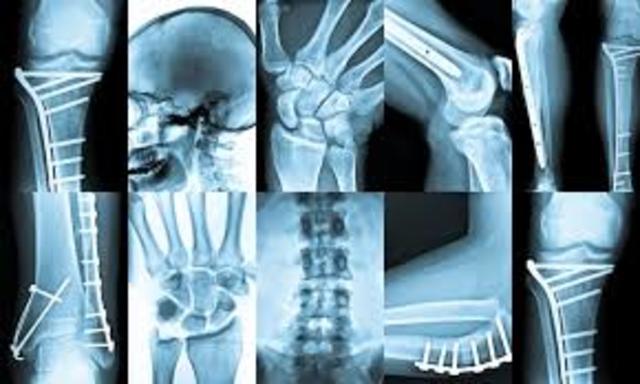

El doctor Montoya Flórez, padre de la cirugía en Colombia, trajo a Medellín el primer equipo de rayos X con el cual se realizó la primera radiografía en Colombia.

Los primeros equipos de mamografía fueron adaptaciones realizadas a los equipos de radiología. En 1980 llega al país la xeroradiografía que se aplicó fundamentalmente en los estudios de los problemas de seno así como en la localización de cuerpos extraños de partes blandas.